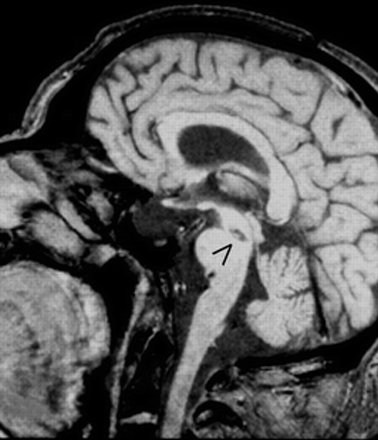

尾中脑病变涉及整个十字交叉的小脑上总花梗非常罕见,但有一种独特的临床征象。偶尔,单方面病变可能产生类似的图片。路易吉Mossuto-Agatiello报告临床和神经影像的光谱发现单边尾中脑梗塞患者。

图。T1 MRI:矢状切面显示尾中脑梗塞。